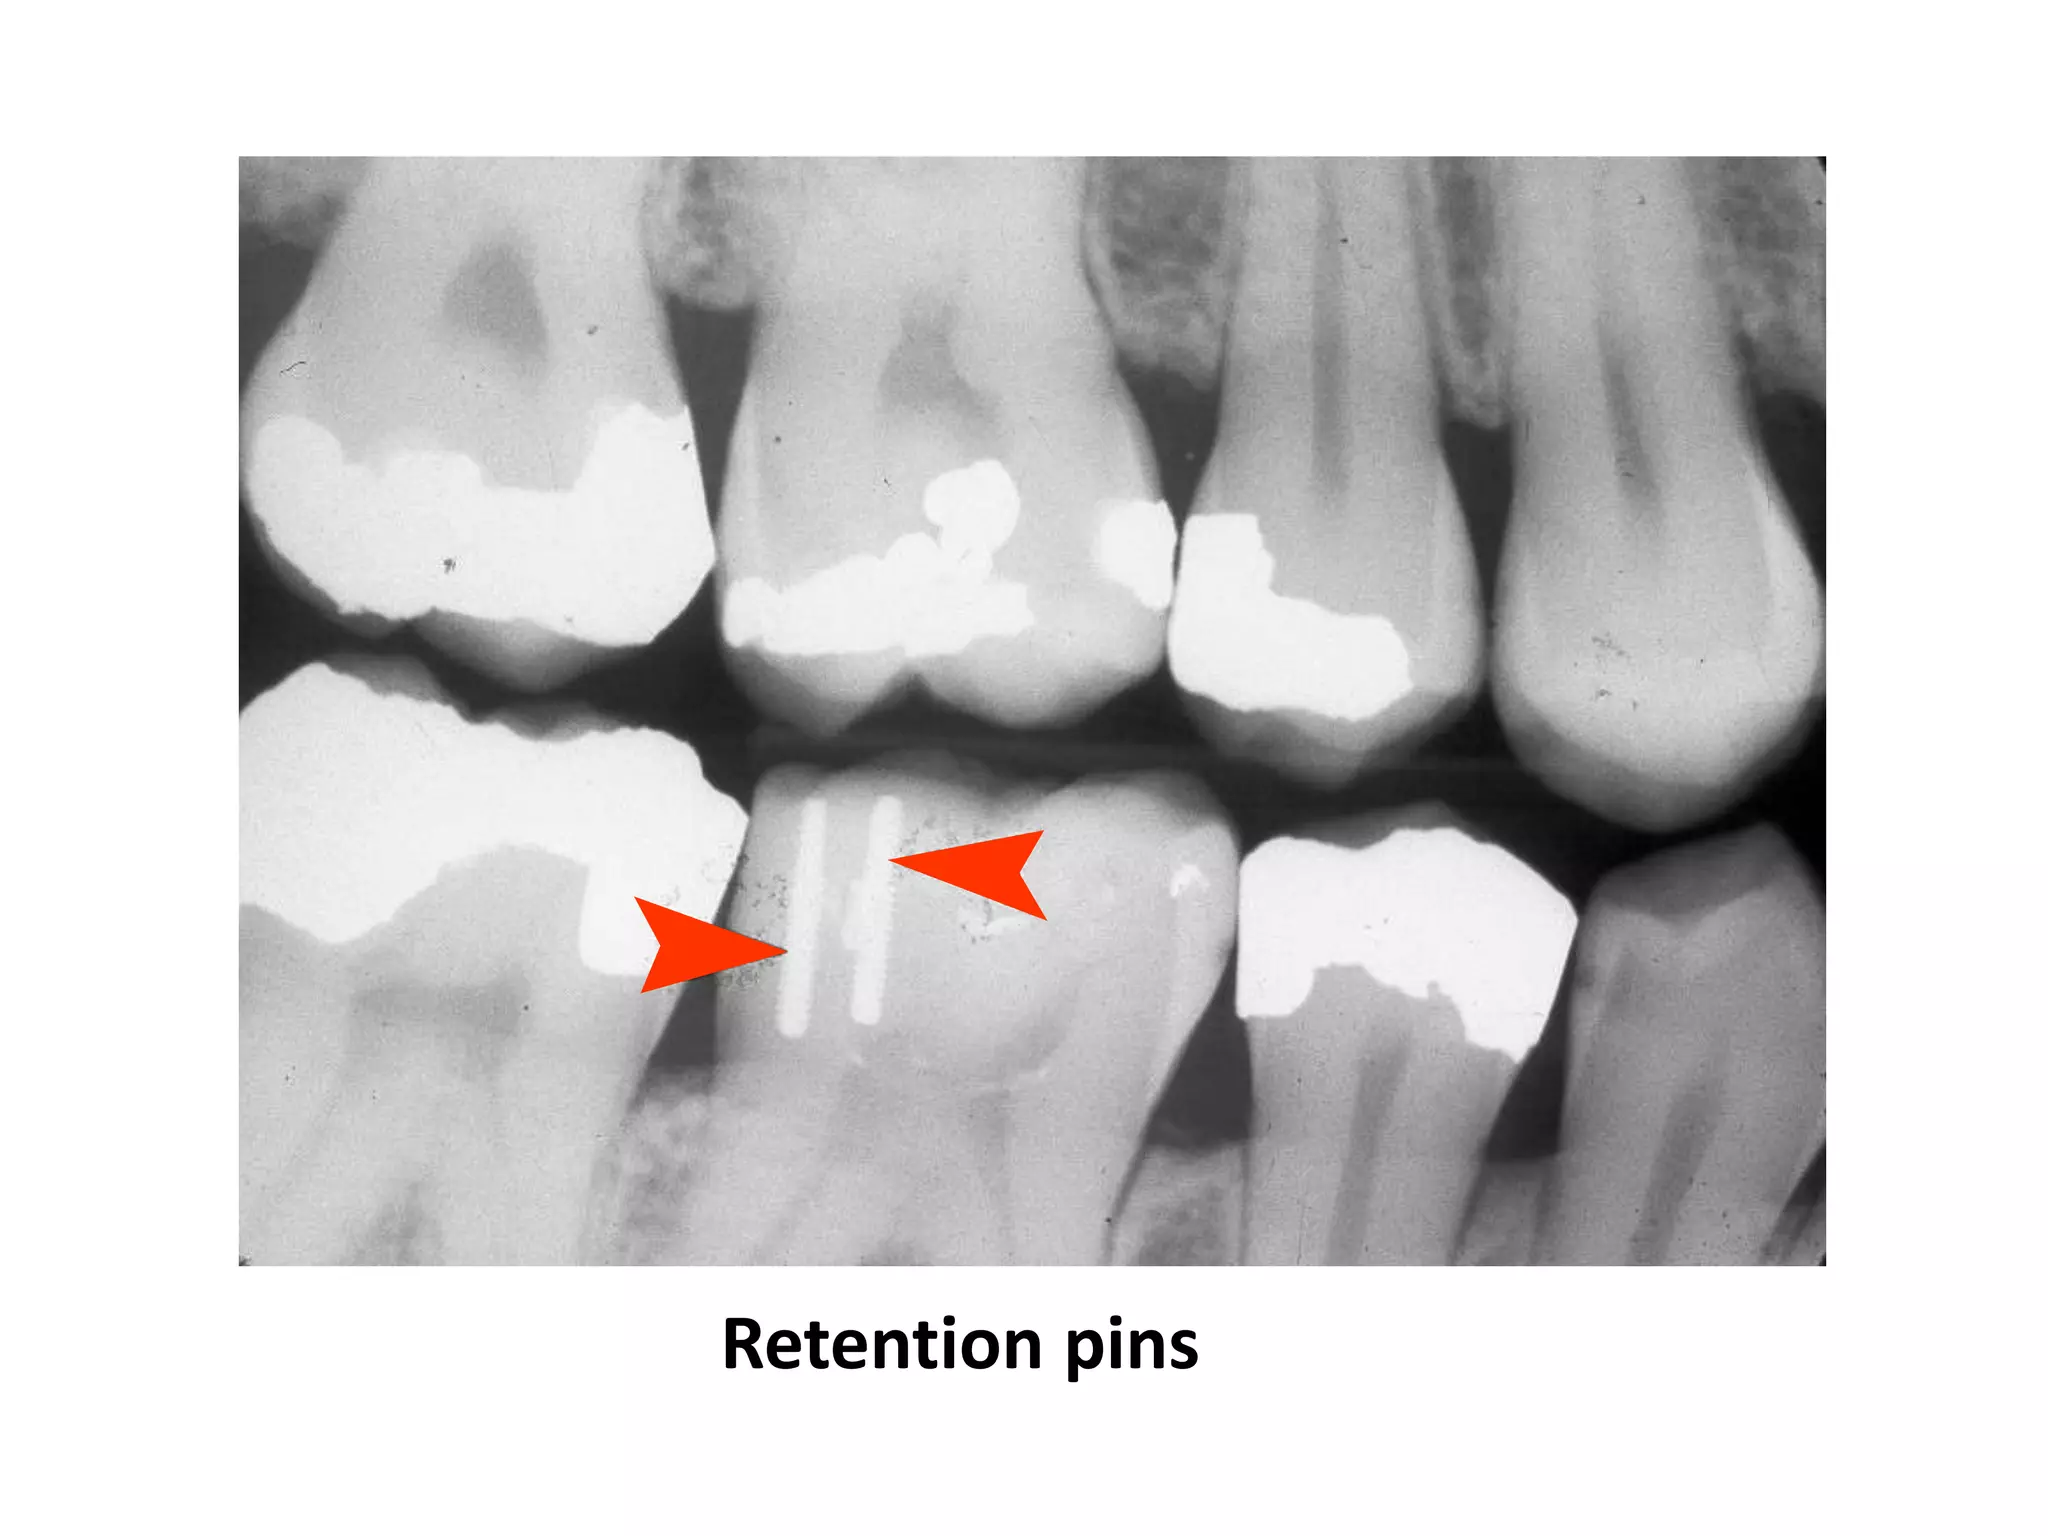

Gold crowns, amalgams

Retention pins

Red arrows point to bases

Green arrow indicates recurrent caries with

fractured restoration